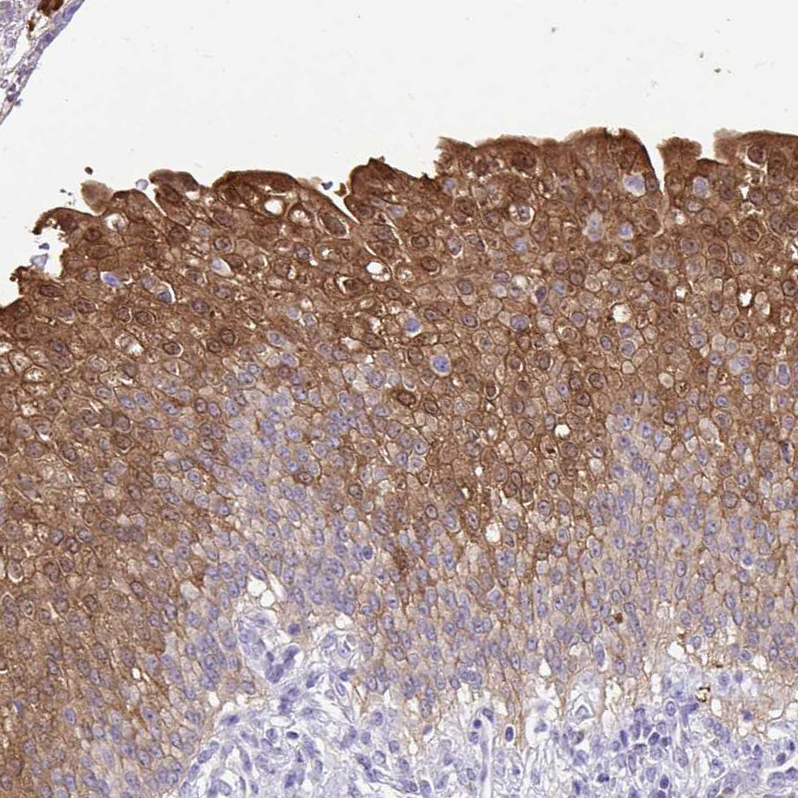

Immunohistochemical staining of human prostate shows moderate cytoplasmic positivity in glandular cells.